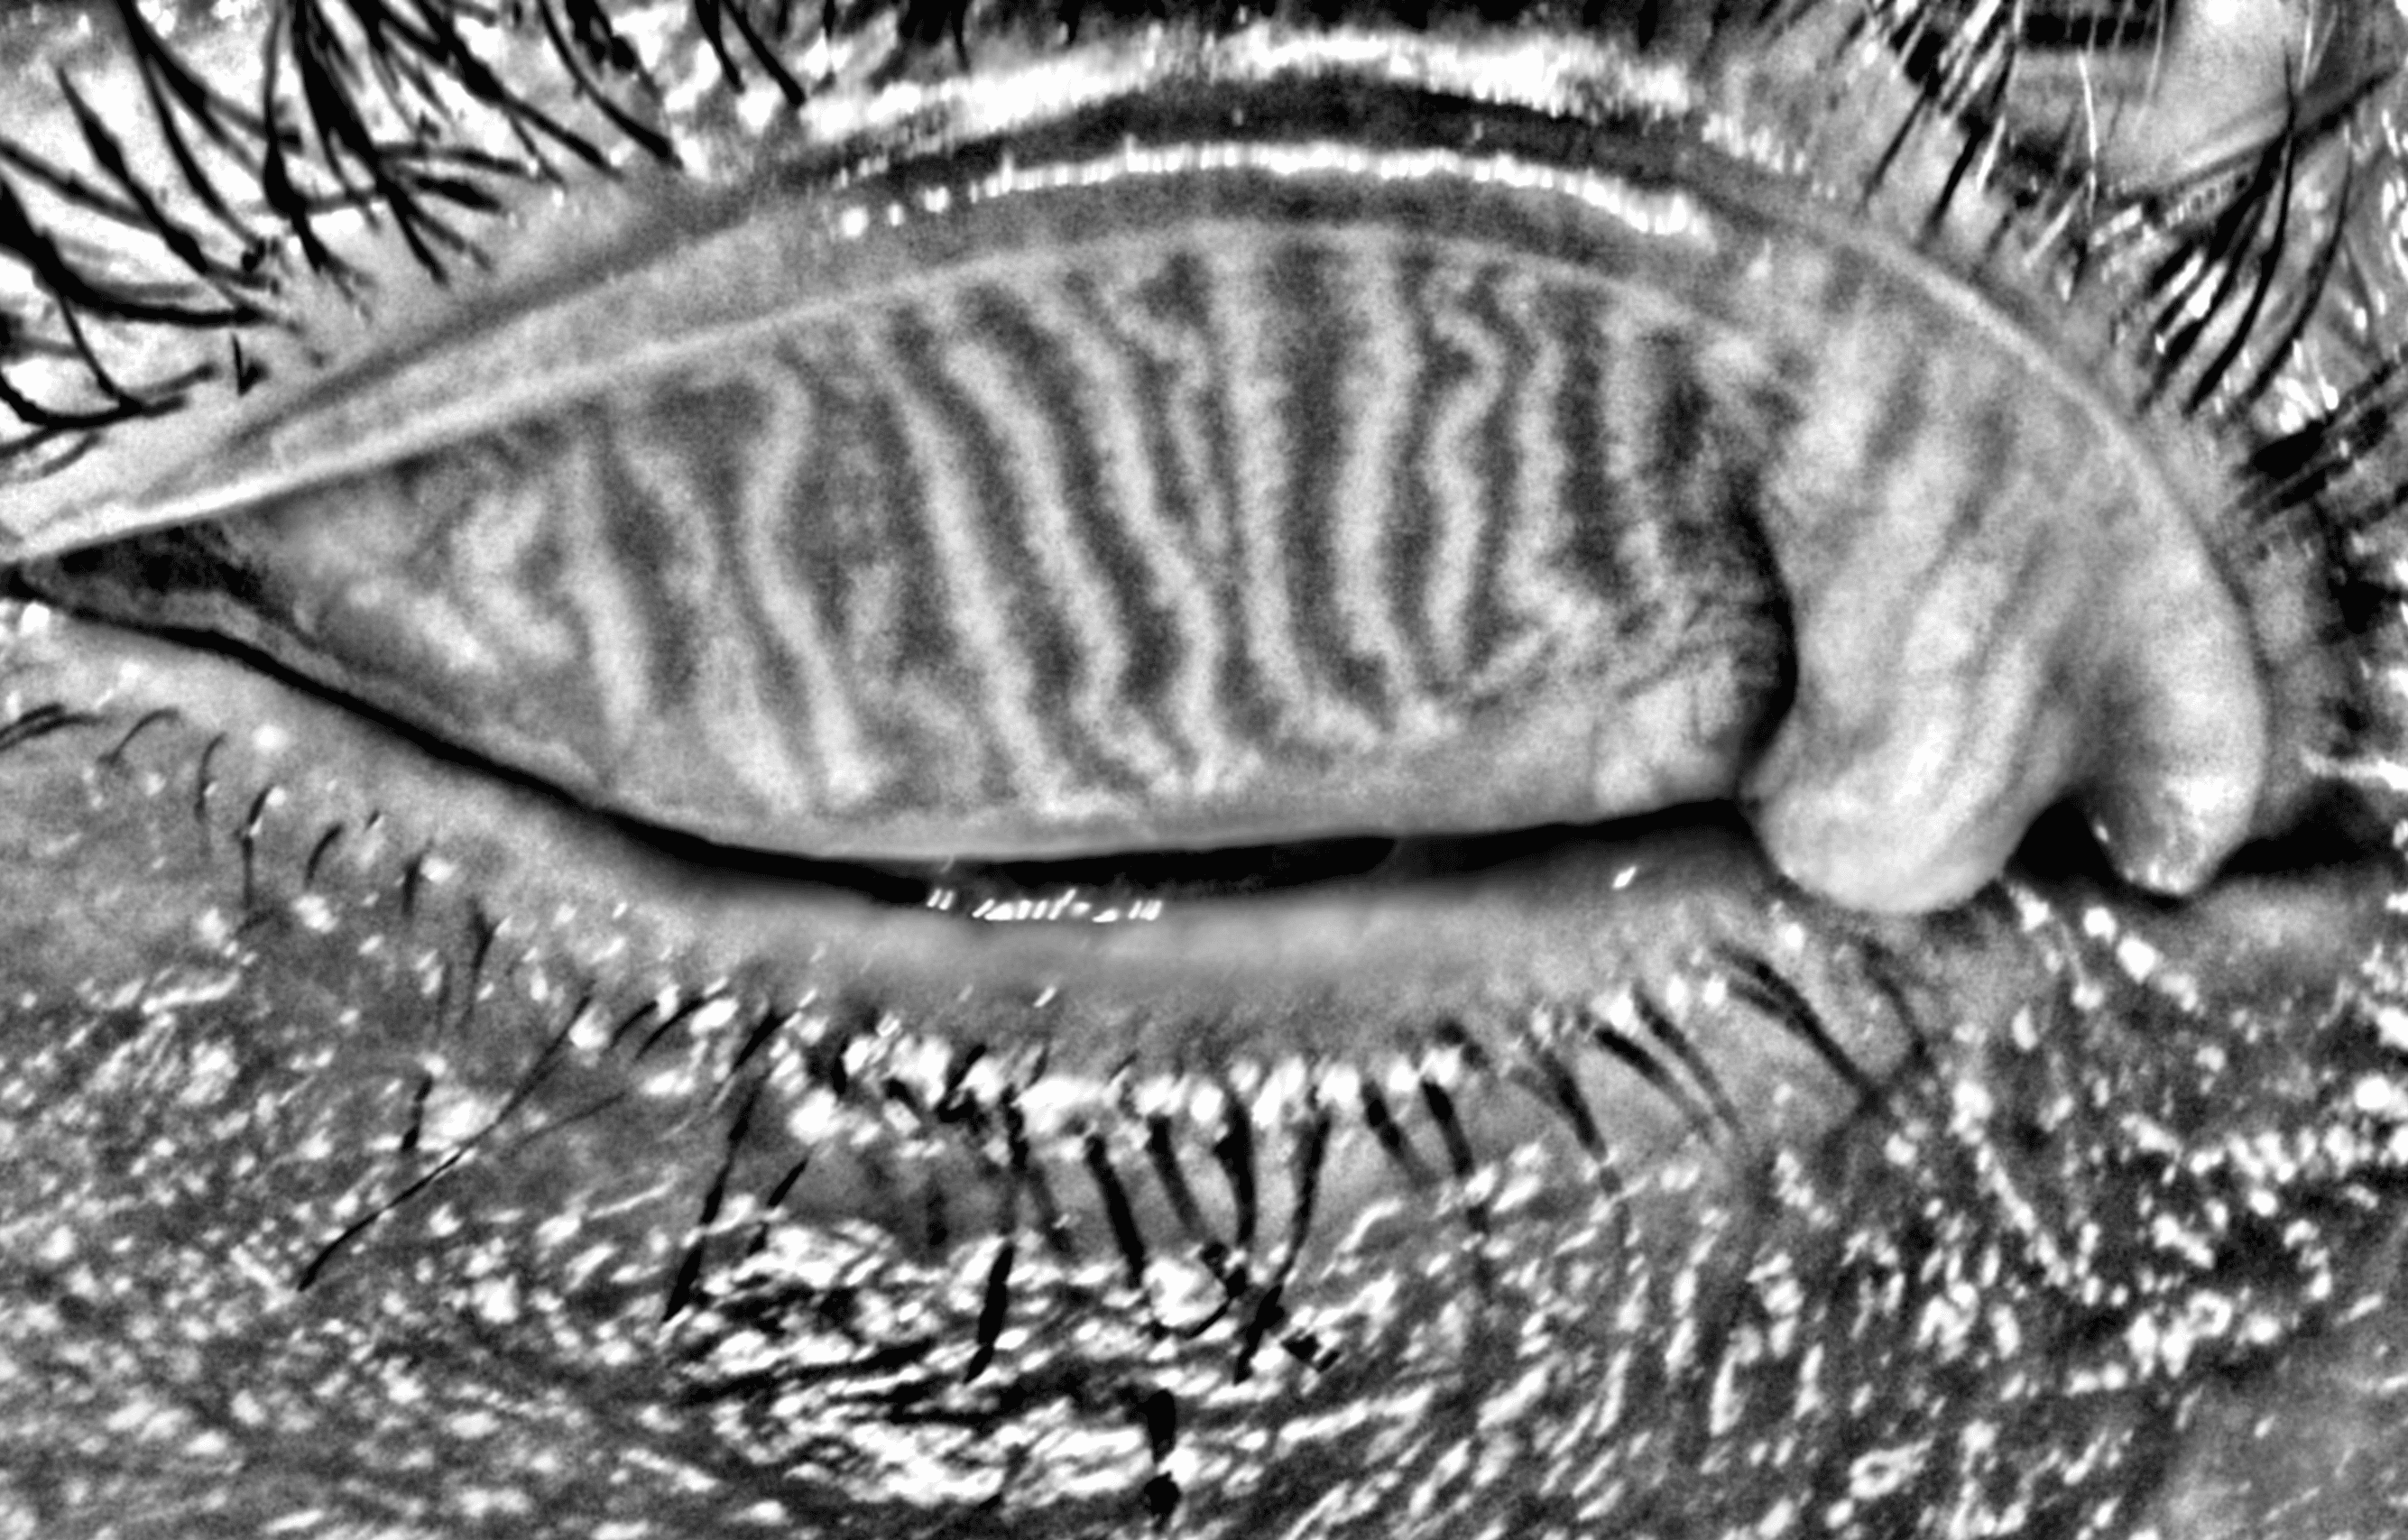

Capture and visualize meibomian gland structure, blink dynamics, tear film appearance, fluorescein imaging, and patient-reported symptoms using a single, compact device designed to integrate seamlessly into existing clinical setups.

AI-Enhanced Visualization

See More with AI-Assisted

Real-Time Visualization

AI-assisted image processing enhances the visibility of ocular surface features, reducing time required manual image adjustments and allowing clinicians to focus on efficient clinical review. Operating directly on the live video stream, it provides immediate visual feedback that supports faster alignment, more confident image capture, and a smoother workflow.